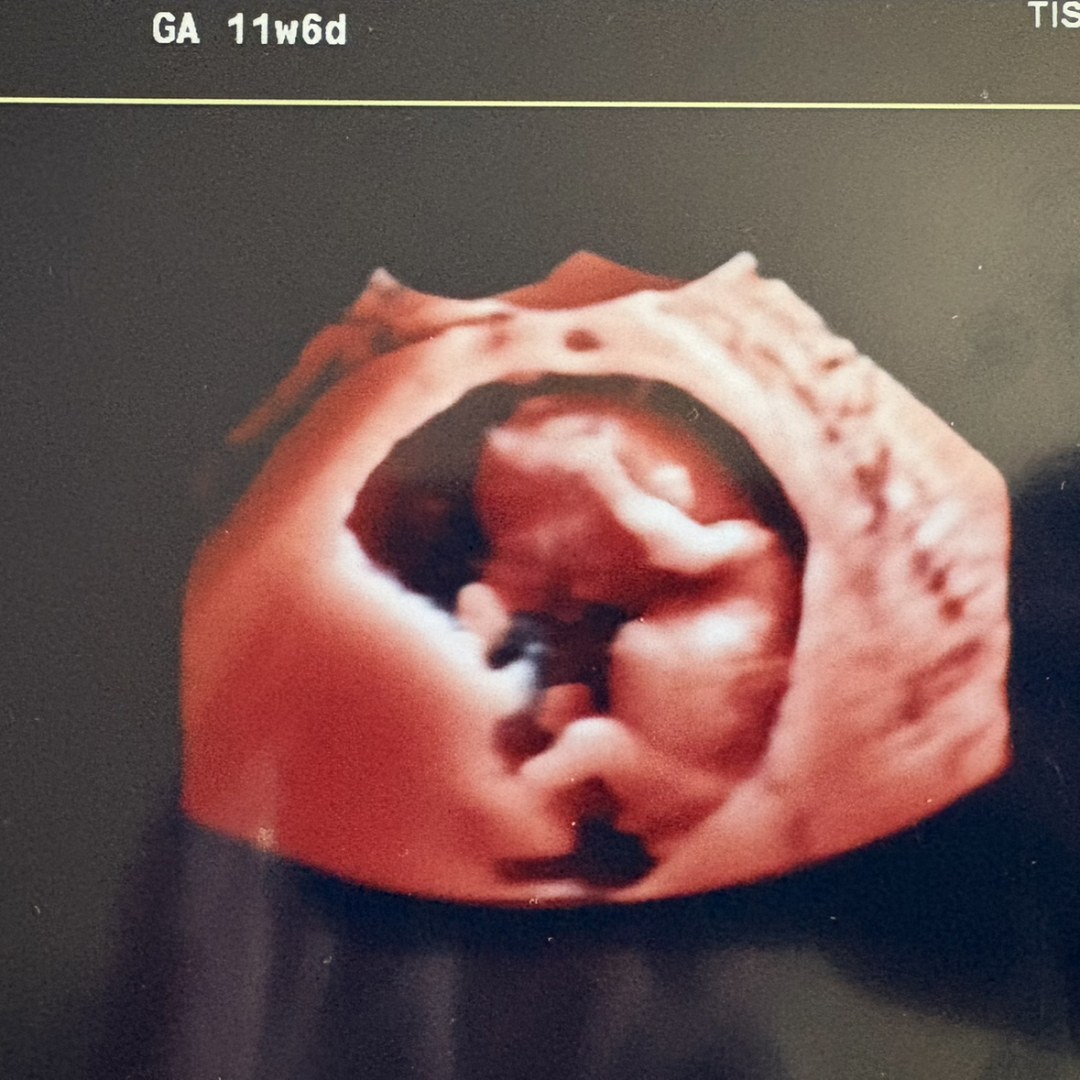

Andrew and I are so excited to welcome a baby boy in April. Thanks in advance for your help and support as we kick off this next adventure!

Baby Boy Lipniskis!